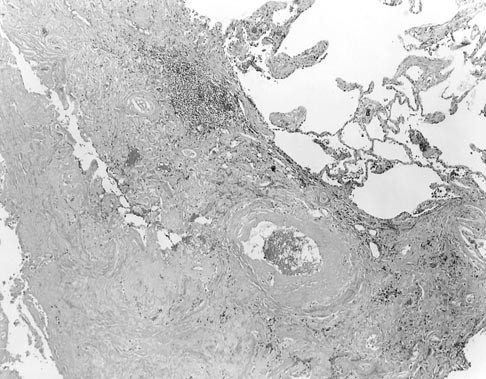

FIGURE 1

Amyloidoma: Sharply demarcated dense amyloid deposits in the lung parenchyma and blood vessels were associated with a scant lymphoplasmacytic infiltrate that was more prominent at the periphery of the nodule than in its center (hematoxylin and eosin stain, original magnification, 16 ×).